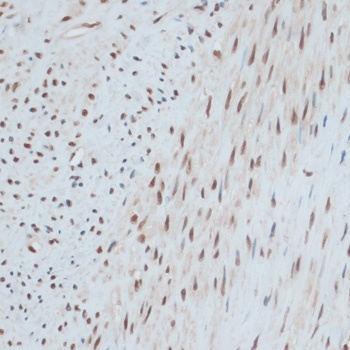

Immunohistochemistry of paraffin-embedded rat brain using ZNF433 antibody (orb1254798) at dilution of 1:100 (40x lens).